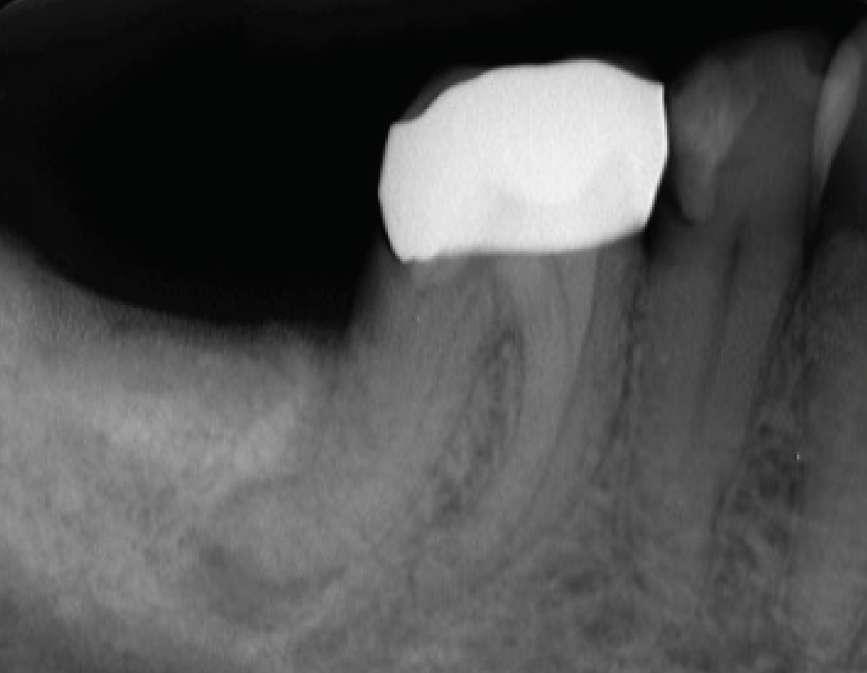

Die Patientin wurde zur Beurteilung und Behandlung von Zahn Nr. 46 an unsere endodontische Praxis überwiesen. Klinisch wies Nr. 46 eine Vollkeramikkrone auf, reagierte negativ auf Kälte und war empfindlich gegenüber Perkussion. Die präoperative Röntgenaufnahme ergab, dass Nr. 46 eine periapikale Radioluzenz an der distalen Wurzel und eine starken Krümmung der D-Wurzel im apikalen Drittel aufwies.

Vor der Operation

Es wurde ein Zugang zu Zahn Nr. 47 erstellt und die Kanäle MB, ML sowie DB und DL lokalisiert. Die Kanäle wurden mit EdgeFile X7-Rotationsfeilen mit einer Crown-DownTechnik instrumentiert.

Konuspassung

Die Arbeitslängen wurden mit dem Apex-Locator bestimmt, gefolgt von einer röntgenologischen Bestätigung. Das Kanalsystem wurde mit BUSA BC Sealer und BC GP Point verschlossen. Der Zugang wurde sofort mit einem faserverstärkten Dual-CureKernmaterial wiederhergestellt.